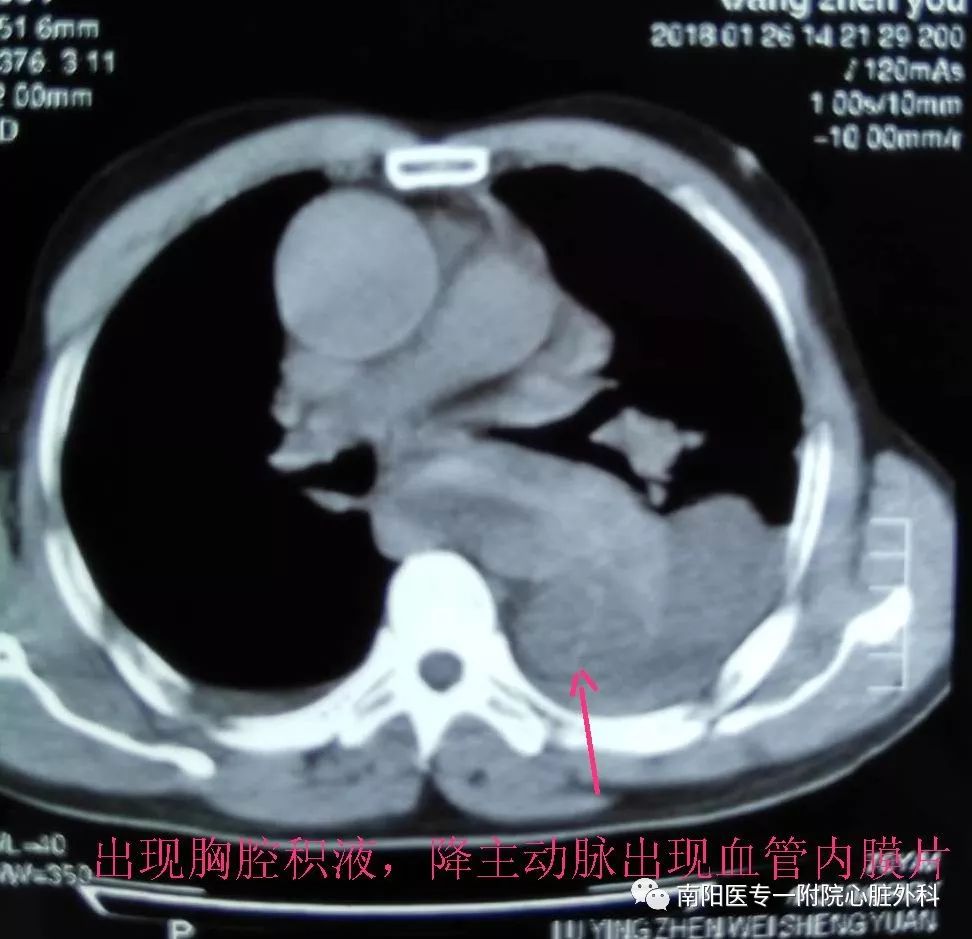

第三天来到我院胸外科住院,我科会诊时发现:患者突发胸背部疼痛,纵膈增宽,气管向右侧移位,声音嘶哑,胸腔积液,CT片上隐约可见降主动脉出现真假腔,高度怀疑主动脉夹层。

立即行CTA,明确诊断为Stanford B 型主动脉夹层,破口位于左锁骨下动脉根部,并且主动脉弓部明显增宽,左侧胸腔大量积液。此种情况非常危险,为主动脉夹层濒临破裂的征象,随时有发生破裂死亡的可能。